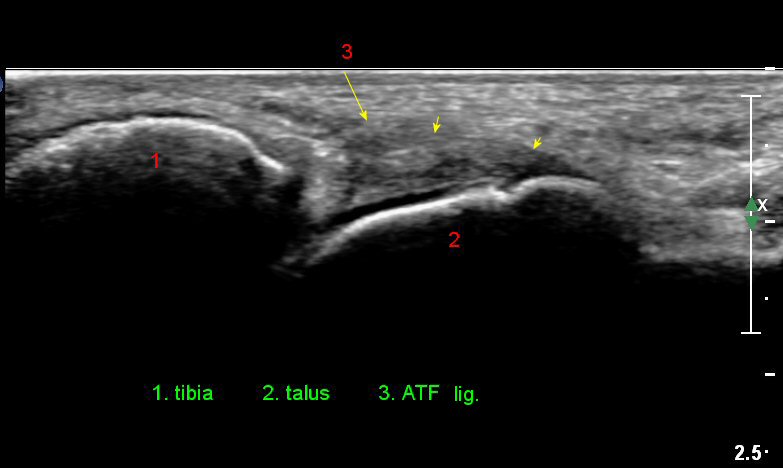

Àü¹æ °æ°ñºñ°ñÀδë Á¾´Ü¸é°Ë»ç¿¡¼­ ƯÀÌ ¼Ò°ßÀ» º¸ÀÌÁö ¾Ê´Â´Ù(»çÁø 3).

Àü°ÅºñÀδë Á¾´Ü¸é°Ë»ç¿¡¼­ ¾È´ë ºñ°ñ ºÎÂøºÎÀÇ Àú¿¡ÄÚ ºÎÁ¾°ú ºÎºÐÆÄ¿­ÀÌ °üÂûµÈ´Ù(»çÁø 4).

¹ß¸ñ°üÀý ¾ÕÂÊ Á¾´Ü¸é°Ë»ç¿¡¼­ °üÀý³» ¼ö¾×Àú·ù°¡ »ç¶óÁö°í(»çÁø 1),

Àü°ÅºñÀδë Á¾´Ü¸é°Ë»ç¿¡¼­ Àü°ÅºñÀδëÀÇ Àú¿¡ÄÚ ºÎÁ¾ÀÌ °¨¼ÒÇϰí ÀδëÀÇ ¿¡ÄÚ°¡

Áõ°¡µÇ¾ú´Ù(»çÁø 3, 4).

Àü°ÅºñÀδë Á¾´Ü¸é°Ë»ç¿¡¼­  Àú¿¡ÄÚ ºÎÁ¾ÀÌ °¨¼ÒÇϰí ÀδëÀÇ ¿¡ÄÚ°¡ Áõ°¡µÇ¾ú´Ù(»çÁø 2, 3, 4).